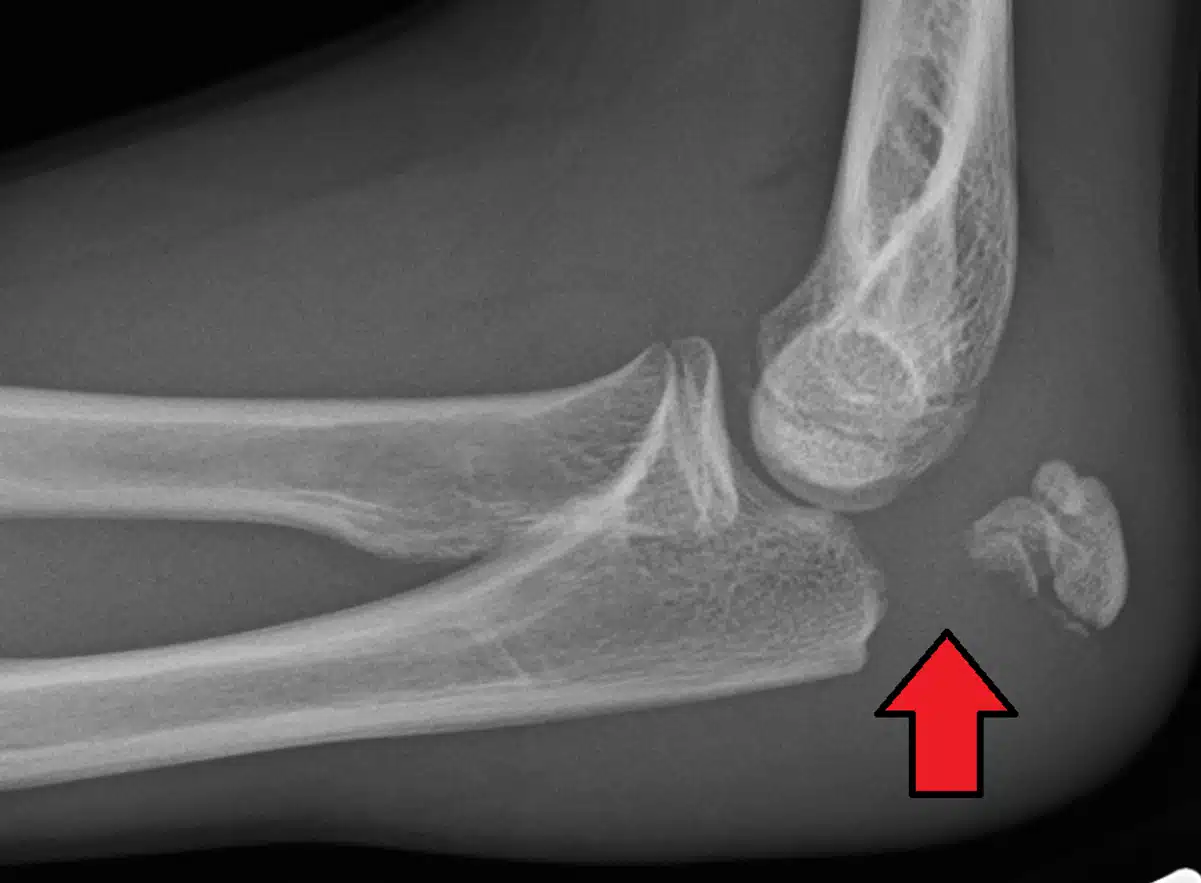

تشخیص بورسیت اولکرانون معمولا با معاینه فیزیکی دقیق آرنج توسط پزشک متخصص ارتوپدی صورت میگیرد. پزشک با لمس ناحیهی آرنج، بررسی تورم، درد و محدودیت حرکتی میتواند به تشخیص اولیه برسد. در برخی موارد، پزشک ممکن است برای تایید تشخیص و بررسی دقیقتر، درخواست انجام آزمایشاتی نظیر رادیوگرافی یا سونوگرافی آرنج بدهد.

اشعه ایکس: برای رد شکستگی یا سایر مشکلات استخوانی